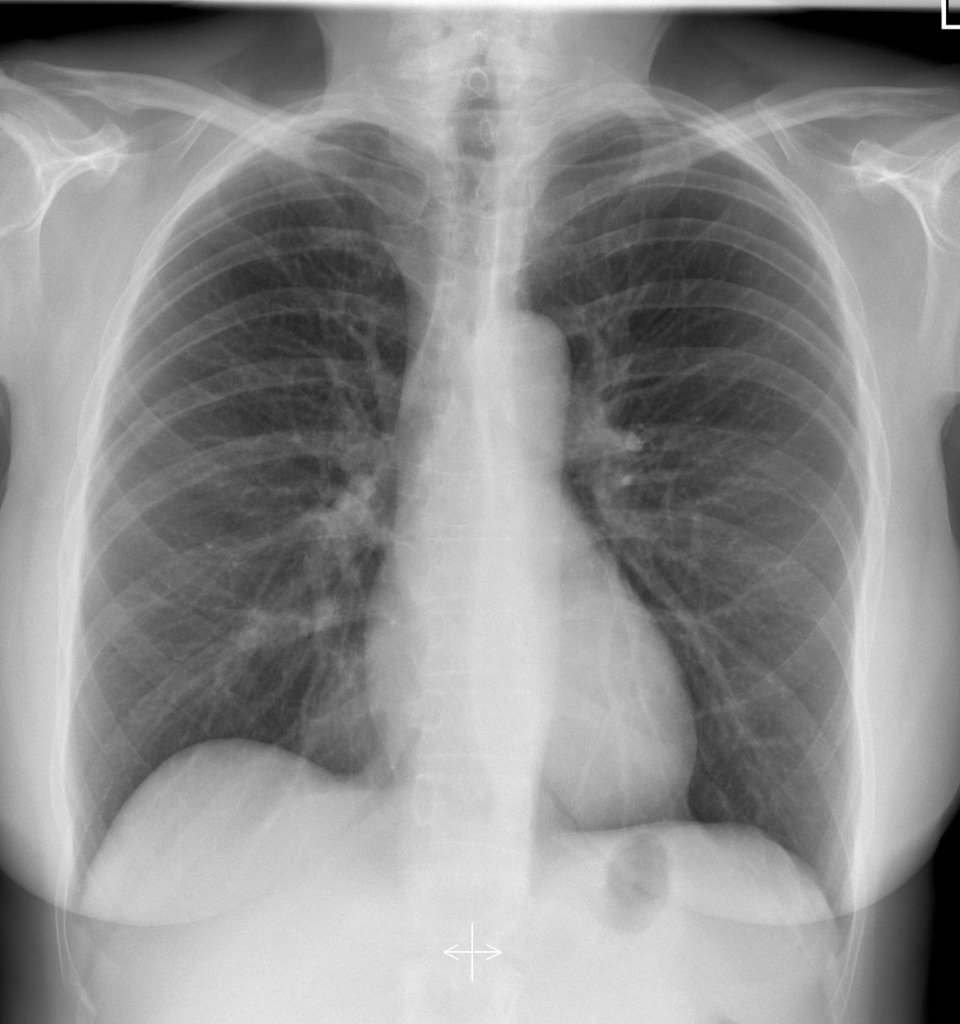

Chest x-ray for the case: